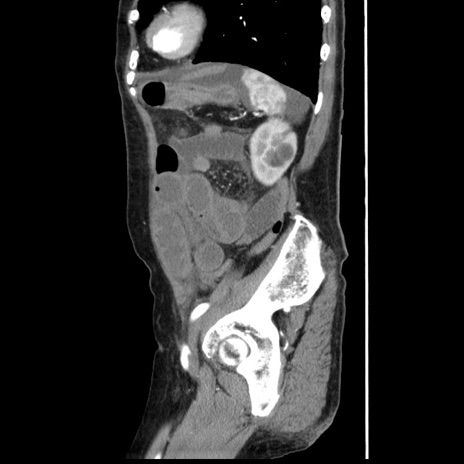

横断像

【症例】80歳代女性

【主訴】腹痛

【現病歴】8時間前から腹痛あり来院。

【既往歴】糖尿病、脂質異常症、子宮体癌にて子宮全摘術

【身体所見】意識清明・会話良好だが腹痛で苦悶様、全腹部にわたって反跳痛と圧痛あり

【データ】WBC 13600、CRP 0.14、LDH 224、CK 90